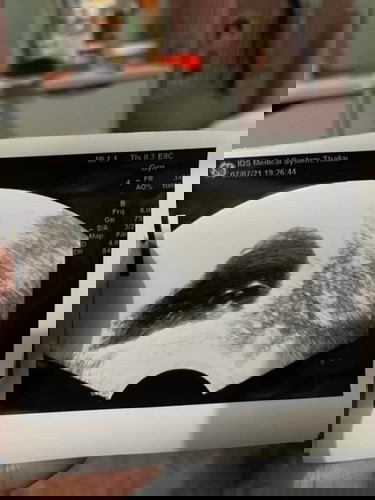

หมอบอกท้องลม 8 วีค 5 วัน

วันนี้หมอนัดเราก้อไปตามนัดปกติ ปรากฎว่าหมอซาวด์ทางช่องคลอด เอาเข้าไปแป็บเดียว หมอเอาออกเลยค่ะ หมอบอกเราท้องลม เราร้องโฮเรยค่ะ หมอให้เรามาทำใจเเล้วนัดวันเอาออกค่ะ เเต่เราทำใจไม่ได้ ใครเคยทีอาการแบบนี้บ้างไหมคะ#ขอบคุณสำหรับคำตอบค่ะ